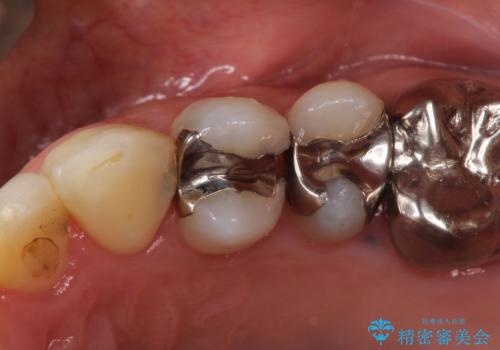

総合歯科治療 → 根管治療&セラミック治療

セラミックインレーと根管治療を伴うセラミッククラウン